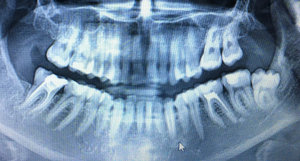

Перед тем как делать операцию, врач должен перестраховаться и сделать рентгеновский снимок. В случае, если зуб ретинированный, желательно сделать несколько снимков с разных ракурсов, для того чтобы расположение корней не вызывало сомнений и операция прошла менее травматично и послеоперационный период не затягивался.

По снимку можно определить насколько вероятно распиливание левого нижнего зуба мудрости?

Комментарий №176331

• Восьмые зубы при таком положении полноценно не прорежутся. Поэтому их рекомендуется удалить. Для доступа к зубу разрезают слизистую и выпиливают небольшой участок костной ткани.